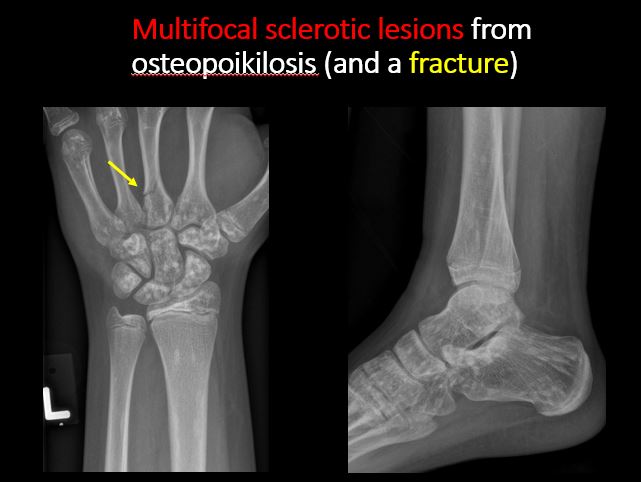

There is/are focal or multifocal lytic/lucent, blastic/sclerotic or mixed density lesion(s) or other abnormality. [Yes/No]